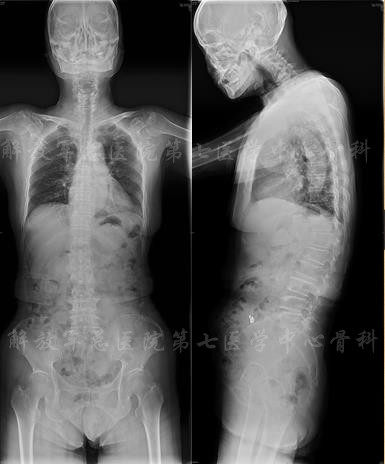

影像学检查

X线片

颈部X线片

X线片:TL cobb 38、PI 53、SS 13、PT 40、LL 9

MRI

MRI颈4-5(左)、颈5-6(中)颈6-7(右)

矢状位MRI

轴位MRI:腰3-4(左)、腰4-5(中)、腰5骶1(右)